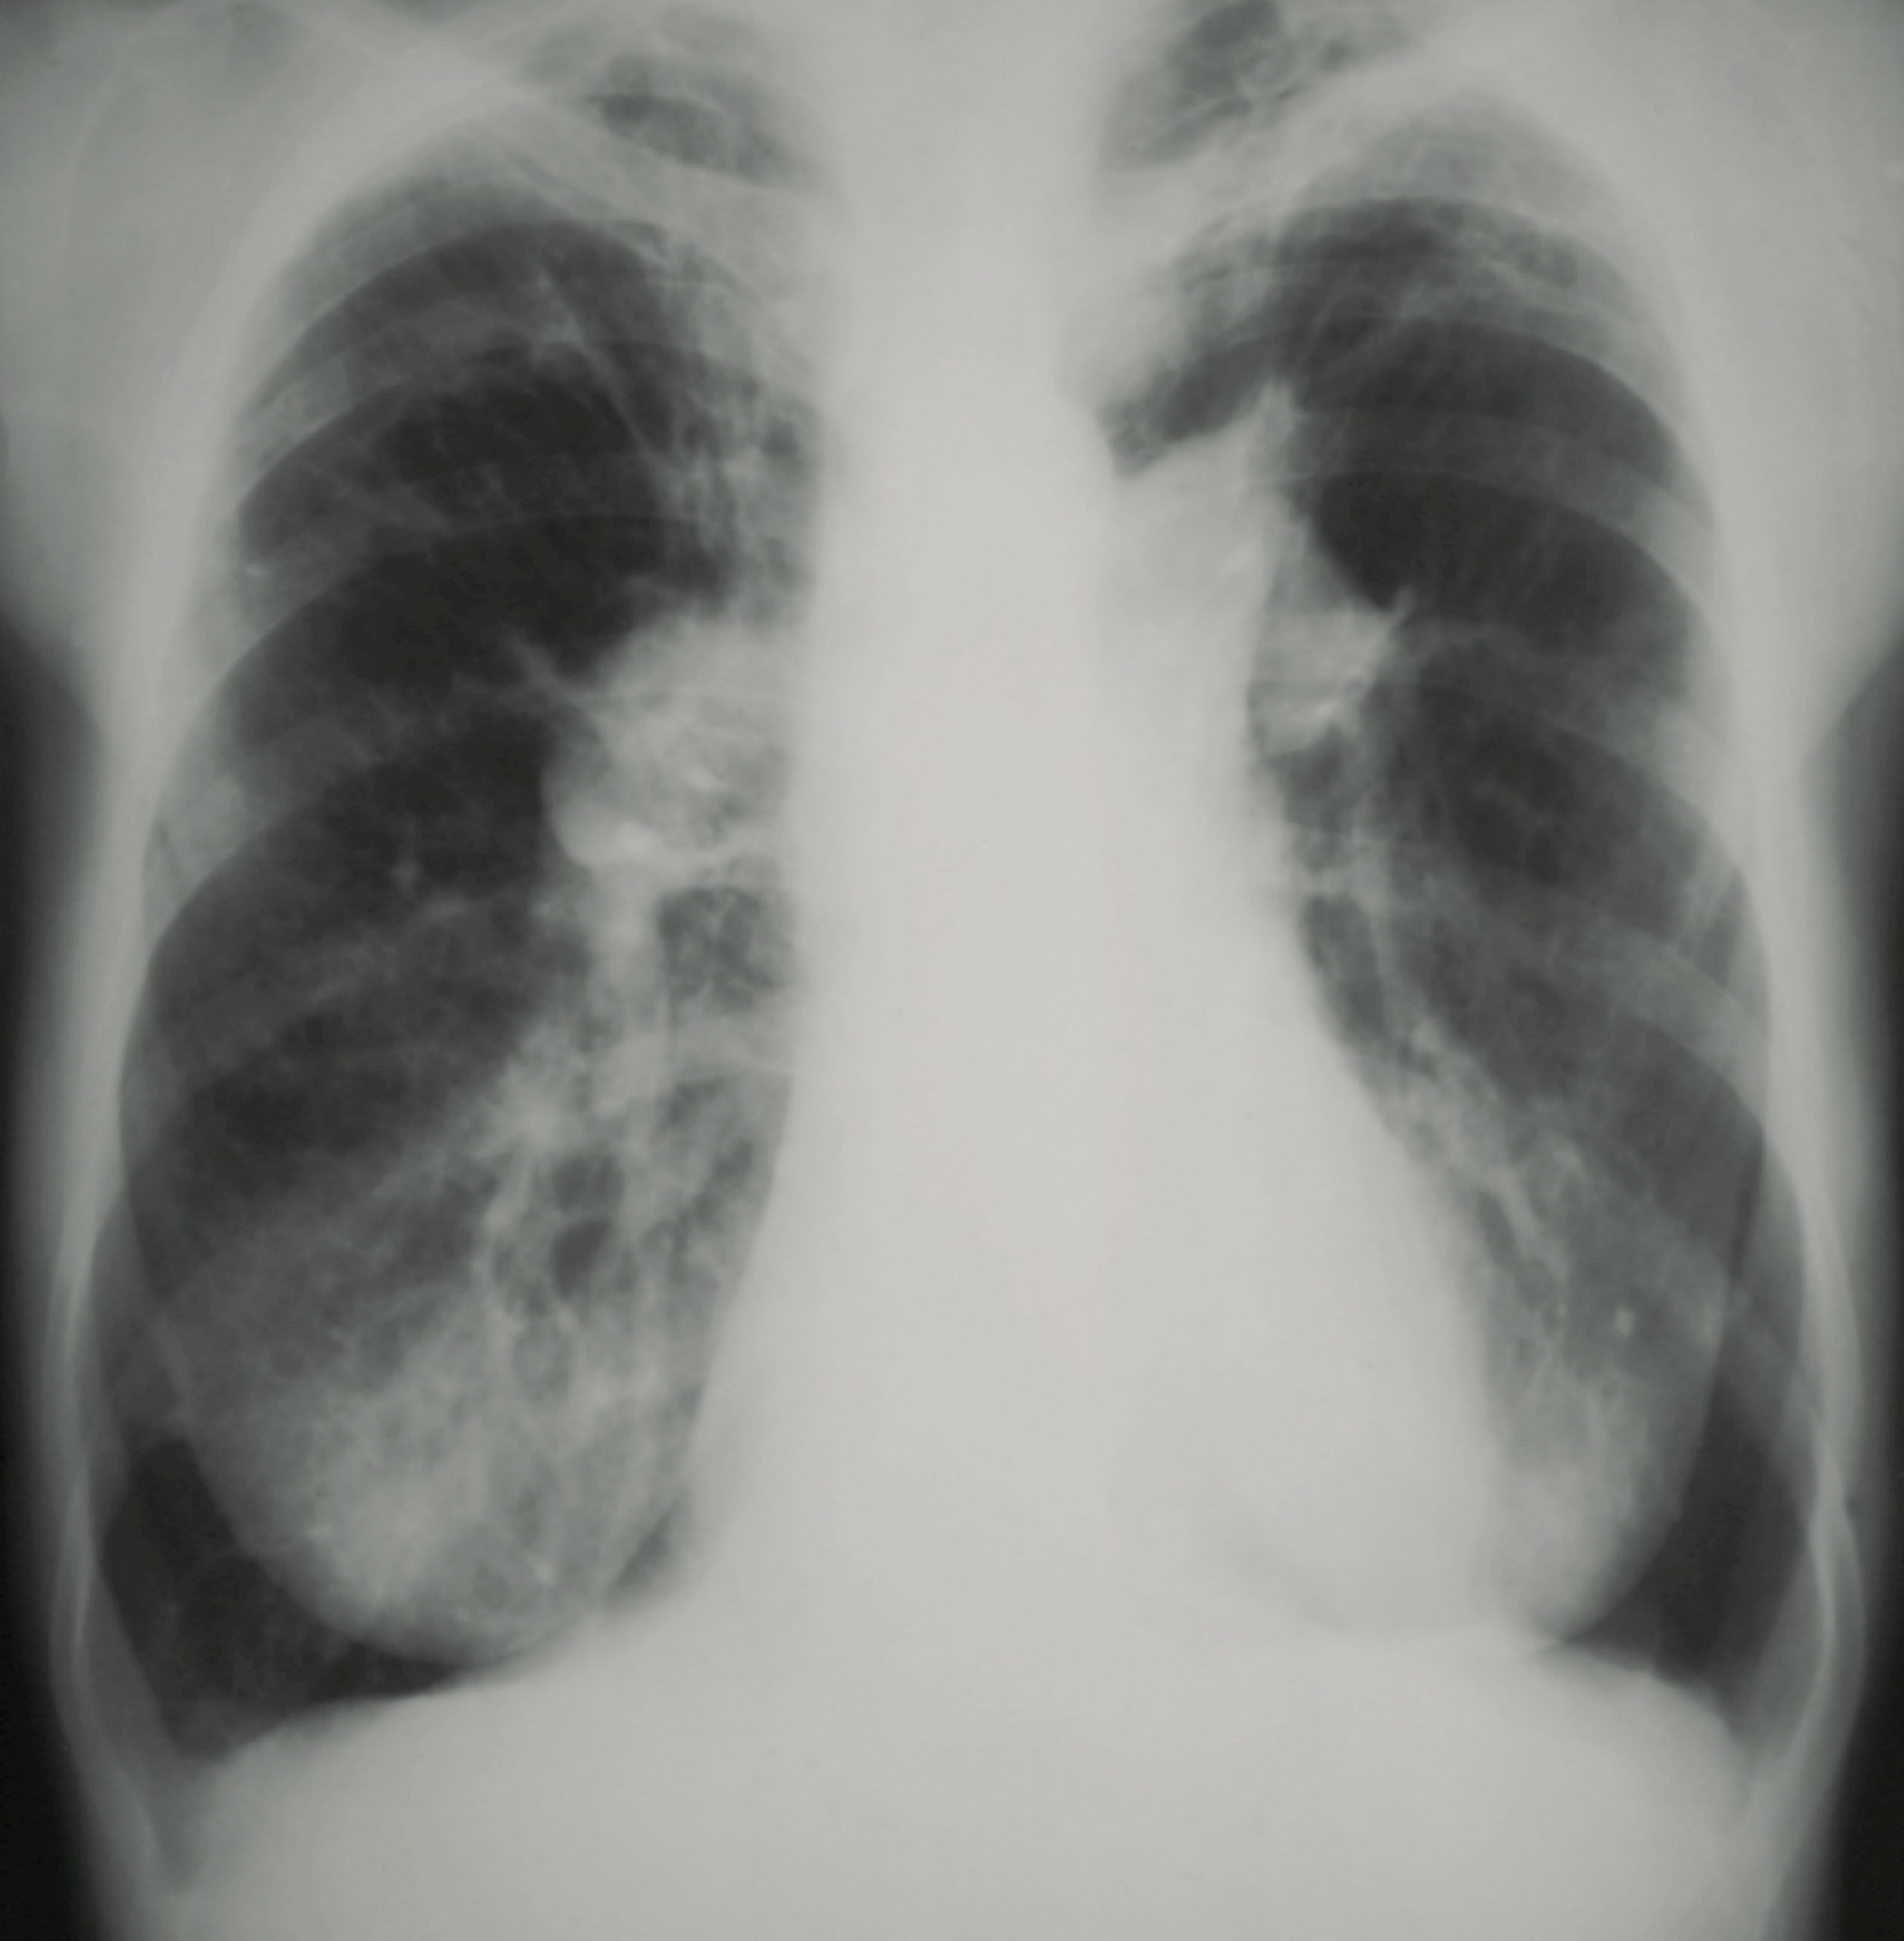

Za diagnozo pljučne hipertenzije so potrebne številne ne-invazivne preiskave (EKG, rentgen pljuč, test hoje, laboratorijske preiskave, CT prsnega koša, scintigrafija pljuč), kot osrednjo pa as. dr. Mlakar omenja ultrazvok srca, vedno pa je potrebna za postavitev diagnoze tudi desnostranska srčna kateterizacija. »Pri slednji na minimalno invaziven način izmerimo tlake v pljučnem krvnem obtoku, kar je krajši poseg, ki se opravlja v bolnišnici v lokalni anesteziji.